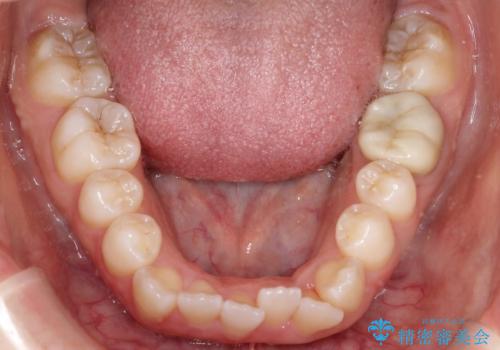

- 前歯のデコボコ(叢生)と、上下の歯が閉じない開口を主訴にご来院されました。精密な検査の結果、歯が並ぶスペースが不足しており、特に奥歯の咬み合わせが安定していないことが開口の原因と判明。患者様と相談し、上下左右の小臼歯を抜歯することでスペースを確保し、審美ワイヤー矯正で全体を整える治療計画を立案しました。これにより、見た目の改善だけでなく、機能的な咬み合わせも獲得することを目指します。

今回の矯正治療では、歯が並ぶスペースを確保するため、上下左右の小臼歯を抜歯しました。装置には目立ちにくい審美ワイヤーを使用し、見た目に配慮しながら治療を進めました。抜歯によってできたスペースを利用して歯を並べ、前歯のデコボコを解消。同時に、歯列全体を動かすことで、上下の歯がきちんと閉じる開口も改善しました。治療期間は約2年間。治療の結果、コンプレックスだった前歯のデコボコと開口が解消され、整った美しい歯並びと、しっかり咬める機能的な咬み合わせを獲得していただけました。